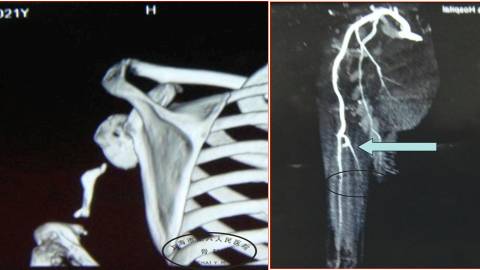

这是一个男性26岁,因为高压电击伤,使右肩部整个上臂开放性损伤。

我们现在遇到的问题,除了右肩部,皮肤软组织缺损以外,还有一个,肱骨长段的骨坏死。

我们首先利用,显微外科的技术,设计一个代替的背阔肌皮瓣,覆盖这个肩部的骨外露的创面,然后同时切取一个游离腓骨的皮瓣。

因为坏死骨切除有11公分,所以我们用腓骨的复合组织瓣,然后吻合血管,用支架进行固定。

手术后两年,可以看到,腓骨得到完全的愈合,而且进行重塑,逐渐的增粗。

他的功能也获得了一个比较满意的恢复。

从X光片上可以看到,她的肱骨全长是缺损的,但是肩关节还有一部分肱骨头的存在。

我们在CT可以看到,这个头还是有一些基本结构,DSA也可以看到,她有足够吻合的血管。